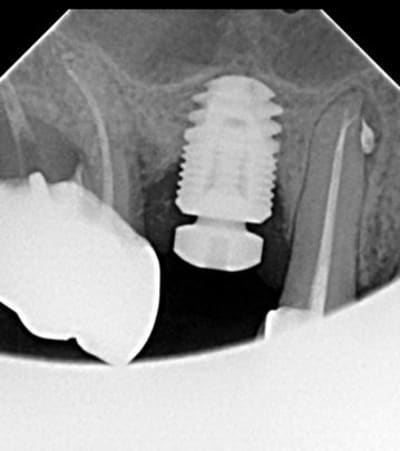

Pour la péri-implantite on ne le voit pas sur la radio mais il y a une perte plus importante en vestibulaire j'ai déjà effectué un débridement après avoir levé un lambeau et on attend qq mois pour la réévaluation.

Vue la largeur de l'implant, je soupçonne qu'il ne devait pas y avoir d'os en vestibulaire.... De plus c'est un implant SOUS CRESTAL en non pas juxta. En juxta j'ai remarqué qu'il y avait fréquemment une cratérisation qui se stabilise (pas un pb paro. pour l'instant).

Pour le moment la dépose n'est pas assurée mais vu la perte osseuse en vestibulaire ainsi que l'hygiène perfectible du patient, la pérennité me semble compromise...

Cher confrère, l'image semble montrer une lésion sur la molaire, d'où ma question. Cette molaire semble mal en point. La perte osseuse sur l'implant est aussi visible, mais bon ça semble pas plus vous déranger.

Je plaisantais Ceramik (d'où le petit ^^)! La molaire est clairement plus préoccupante que l'implant, et posera problème avant.

Et la premo ???

Surtout qu'un pilier de hauteur faible (1.5 ou pire 0.7) aura probablement été utilisé ici en gros diamètre pour créer ce cratère.

Si on enfoui l'implant, un avantage est de préparer le profil d'émergence depuis la profondeur, avec un pilier peu large et haut (ex: diam. 4, htr 3).

Pilier large et bas = compression tissulaire = cratère.

Effectivement, pas dit que ce soit prioritairement infectieux. Peut-être stabilisable, voire reconstructible. Bonne idée de mettre sous pro un temps. Mais vire les piliers inférieurs à 1.5 (idéal 3 quitte à retailler), et si 1.5 (jaune), pas large.